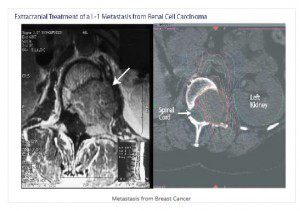

Η θεραπευτική επιλογή εξαρτάται από τον ιστολογικό τύπο της νόσου, το μέγεθος της βλάβης, τον αριθμό των βλαβών και την θέση τους, την παρουσία συμπτωμάτων, την εξωκρανια νόσο, την ηλικία, την κατάσταση ικανότητας του ασθενούς και τις προηγούμενες θεραπείες.

Σε γενικές γραμμές, σε ασθενείς με προσδόκιμο ζωής >6μηνων και με ελεγμένη την εξωκρανια νόσο, οι μονήρεις μεταστάσεις αντιμετωπίζονται είτε με χειρουργική επέμβαση είτε με στερεοτακτική ακτινοχειρουργική. Σε ασθενείς με 1-3 δευτεροπαθείς εγκεφαλικές εντοπίσεις επιλέγουμε την ακτινοχειρουργική.

Η χειρουργική επέμβαση αποτελει θεραπεία εκλογής κυρίως σε συμπτωματικές ευμεγέθεις εστίες για άμεση αποκατάσταση των νευρολογικών συμπτωμάτων ή και για την ιστολογική ταυτοποίηση της νόσου.

Στις περιπτώσεις όπου υπάρχουν πολλαπλές εγκεφαλικές μεταστάσεις (>4) ή σε ασθενείς επιβαρημένους, αυτές αντιμετωπίζονται με ακτινοθεραπεία εφολοκλήρου του εγκεφάλου.

Σε μονήρεις ή και σε περισσότερες της μίας εγκεφαλικές μεταστάσεις ή/και που εντοπίζονται σε χειρουργικά δυσπρόσιτες περιοχές, το CyberKnife® αποτελεί μέθοδο πρώτης επιλογής αφού η χειρουργική αφαίρεση αυτών είναι δύσκολη έως αδύνατη.